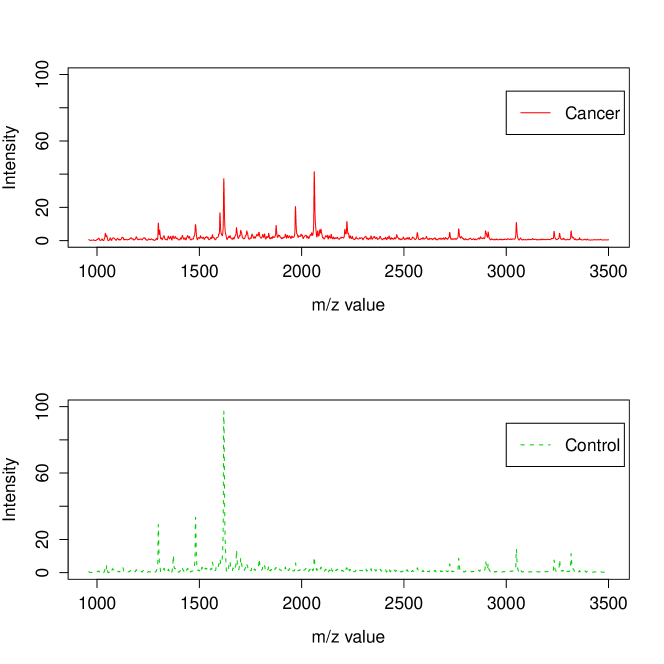

Following the experimental protocol of [3], Fisher-EM was applied on the 6 168 dimensions corresponding to m/z ratios between 960 and 3 500 Da since there is no discriminative information on the reminder. Figure 8 shows the mean spectra of the cancer and control classes estimated by Fisher-EM on the m/z interval 900–3500 Da. To be able to compare the clustering results of Fisher-EM, PCA-EM and mixture of PPCA (Mixt-PPCA) have been applied to this subset as well. It has been asked to all methods to cluster the dataset into 2 groups. It is important to remark that this clustering problem is a problem and, among the model-based methods, only these three methods are able to deal with it (see Section 4.6).

Table 7 presents the confusion tables computed from the clustering results of PCA-EM, mixture of PPCA and Fisher-EM. On the one hand, PCA-EM has selected principal axes with the 90% variance rule before to cluster the data in this subspace and mixture of PPCA has selected principal axes for each group. On the other hand, Fisher-EM has estimated the discriminative latent subspace with axis to cluster this high-dimensional dataset. It first appears that PCA-EM and mixture of PPCA provide satisfying clustering results on such a complex dataset. However, it is disappointing to see that the PCA-EM make a significant number of false negatives (cancers classified as non-cancers) since the classification risk is not symmetric here. Conversely, mixture of PPCA and Fisher-EM provide a better clustering results both from a global point of view (respectively 89% and 91% of clustering accuracy) and from a medical point of view since Fisher-EM makes significantly less false negatives with an acceptable number of false positives.

More importantly, Fisher-EM provides information which can be interpreted a posteriori to better understand both the data and the phenomenon. Indeed, the values of the estimated loading matrix , which is a matrix here, expressed the correlation between the discriminative subspace and the original variables. It is therefore possible to identify the original variables with the highest power of discrimination. It is important to highlight that Fisher-EM extracts this information from the data in a unsupervised framework. Figure 9 shows the correlation between each original variable and the discriminative subspace on an arbitrary scale. The peaks of this curve correspond to the original variables which have a high correlation with the discriminative axis estimated by Fisher-EM.

Figure 10 plots the difference between the mean spectra of the classes cancer and control (cancer - control) and indicates as well, using red triangles, the most discriminative original variables (m/z values). It is not surprising to see that original variables where the cancer and control spectra have a big difference are among the most discriminative. More surprisingly, Fisher-EM selects the original variables with m/z values equal to 2800 and 3050 as discriminative variables whereas the difference between cancer and control spectra is less for these variables than the difference on the variable with m/z value equal to 1350. Such information, which have extracted from the data in a unsupervised framework, may help the practitioner to understand the clustering results.